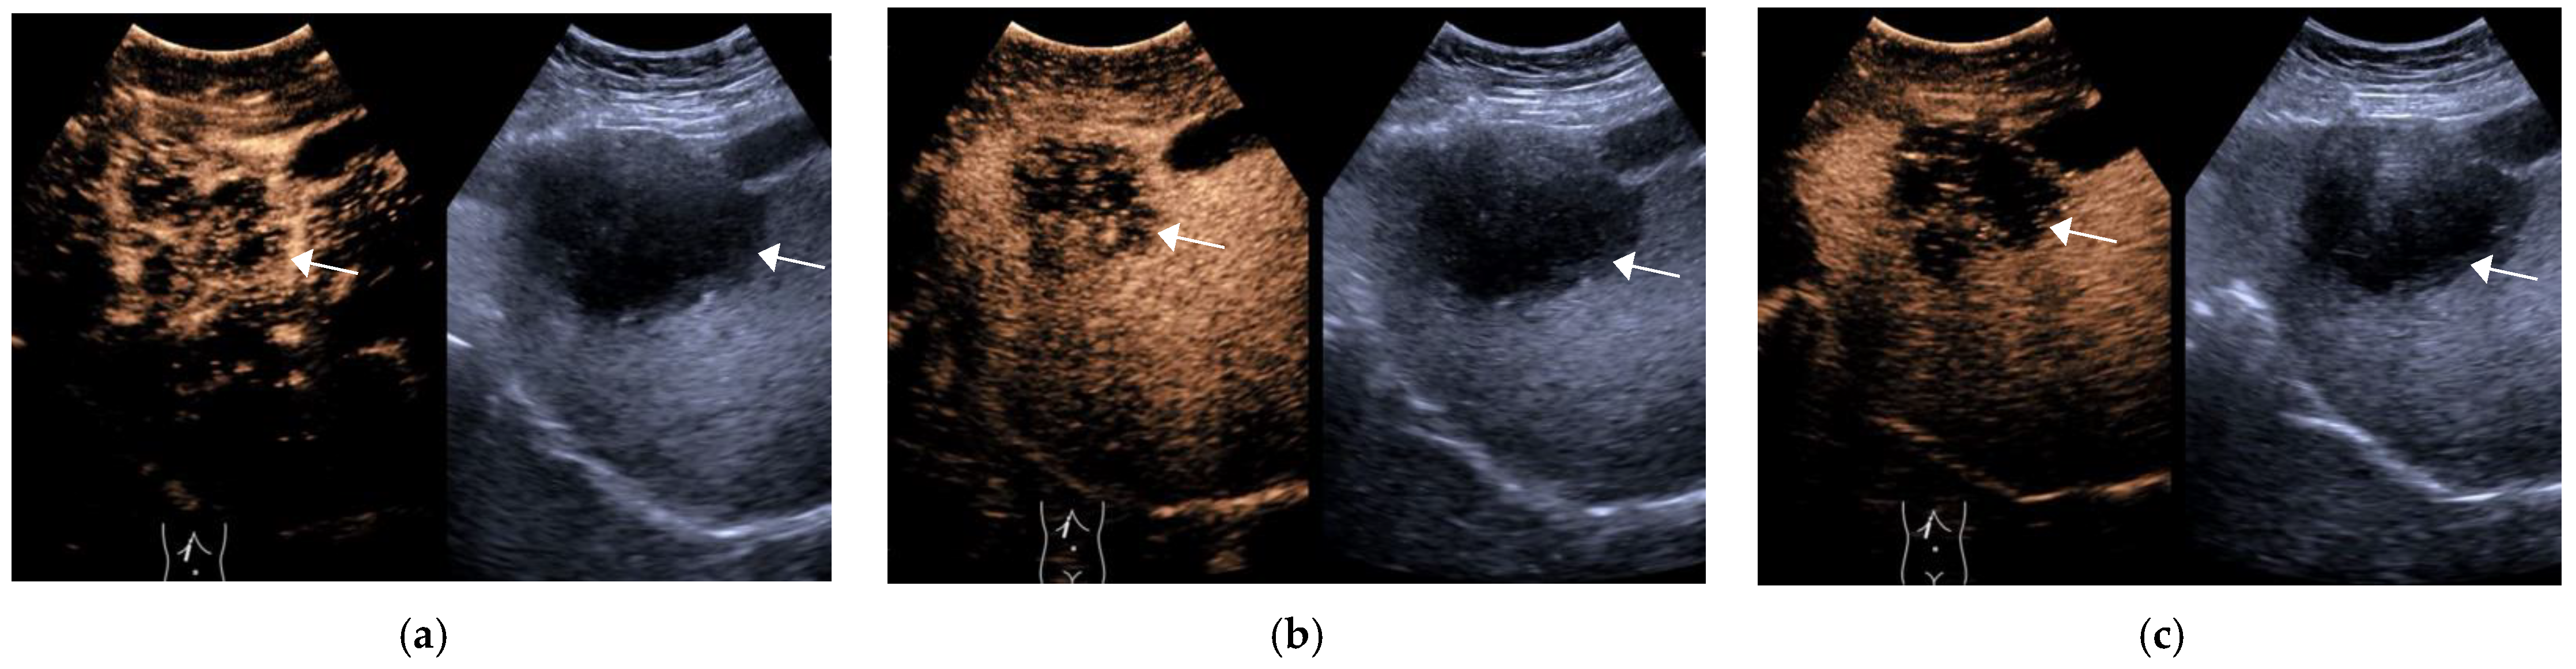

| Group | Num. | Enhancement Pattern in AP | Degree of Wash-Out | Time to Wash Out/s | ||||||

| Non-Rim APHE | Rim APHE | Non APHE | Mild | Marked | Non | <60 | ≥60 | Non-Wash Out | ||

| HCC | 61 | 58 (95.1%) | 2 (3.3%) | 1 (1.6%) | 54 (88.5%) | 3 (4.9%) | 4 (6.6%) | 11 (18.0%) | 46 (75.4%) | 4 (6.3%) |

| OM | 38 | 14 (36.8%) | 22 (57.9%) | 2 (5.3%) | 13 (34.2%) | 25 (65.8%) | 0 (0%) | 32 (84.2%) | 6 (15.8%) | 0 (0%) |

| X2/t | - | 40.745 | 43.373 | 41.946 | ||||||

| p | - | <0.001 | <0.001 | <0.001 | ||||||